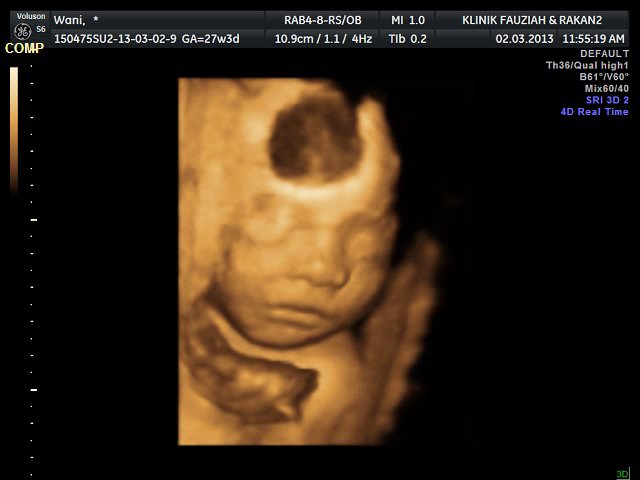

3D (3Dimensi) scan adalah gabungan 2D dalam isipadu (volume) untuk menghasilkan gambar statik luaran rupa bayi..

4D (4Dimensi) pula adalah imbasan 3D yang bergerak..dengan kata lain ia merupakan pengimbasan siaran langsung (video)..so kita boleh melihat bayi bergerak, menguap dan lain-lain..yang pasti bukan 4D nombor ekor tu ye..

jeng..jeng..jeng..bundle jr was here..salam kenal makcik dan pakcik semua..nama kita.. errr..tah..tanya papa..hahaha...

tido pon senyum.lulz..

ni macam buat duckface je..sapa ajar ni?

tu la ko, aku dah tulis ko tak baca..hahaha..2D tu hitam putih ok, yang gambar berwarna atas tu kira 3D je lagi..tapi tetap sama gamba yang keluar kat 4D.. cuma 4D tu dalam format video dan bergerak la..aku screen shoot gambar2 ni dari video tu jugak..hahaha..